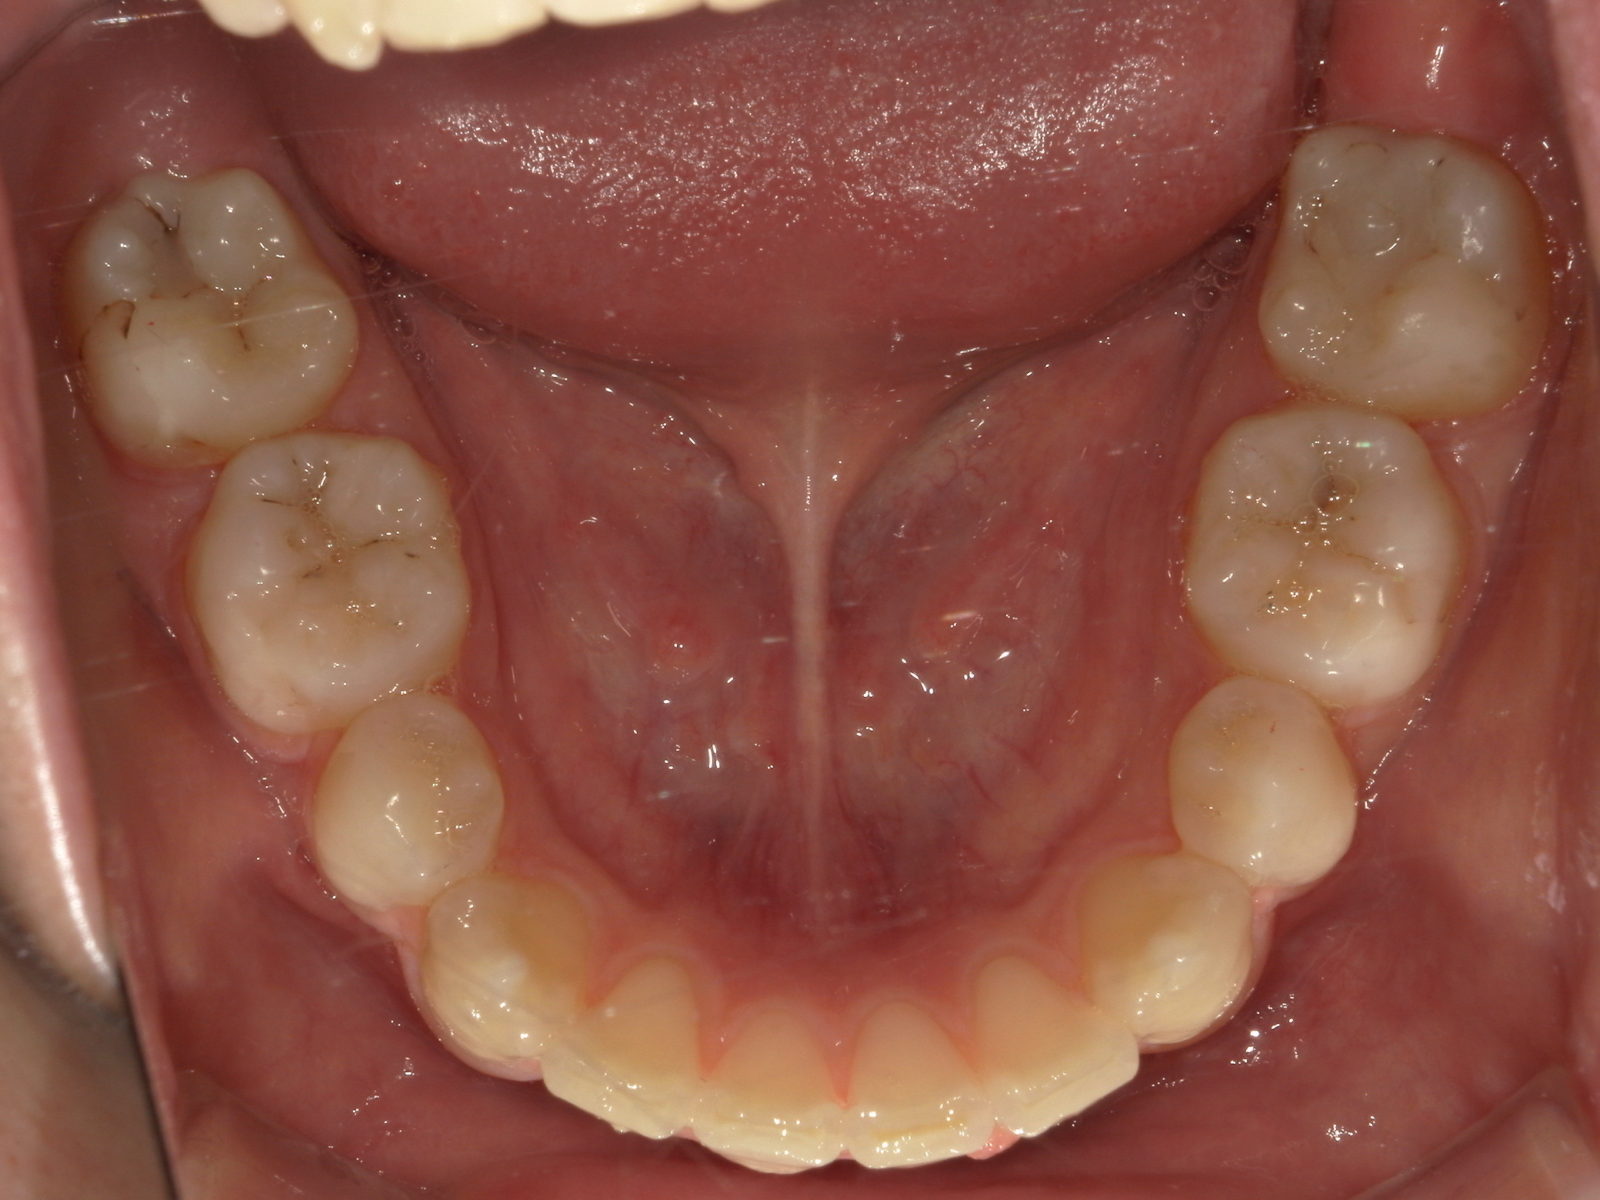

• 治療前

• 治療後

【主訴】歯のガタつき

【診断結果】叢生

【治療開始時の年齢】33歳

【治療内容】表側ワイヤー矯正+マウスピース型 (カスタムメイド) 矯正装置

【抜歯部位】上下左右4番目

【治療経過】後戻り無

【治療期間】2年6ヶ月

【治療費用】1,111,000円

【リスク・副作用】

治療初期の段階では痛みや不快感が生じる可能性がある。適切に歯磨きをしないと虫歯になる可能性が高くなる。個人差により予想された治療期間より長くなる場合がある。治療後はリテーナーを装着しないと後戻りしてしまうリスクがある。